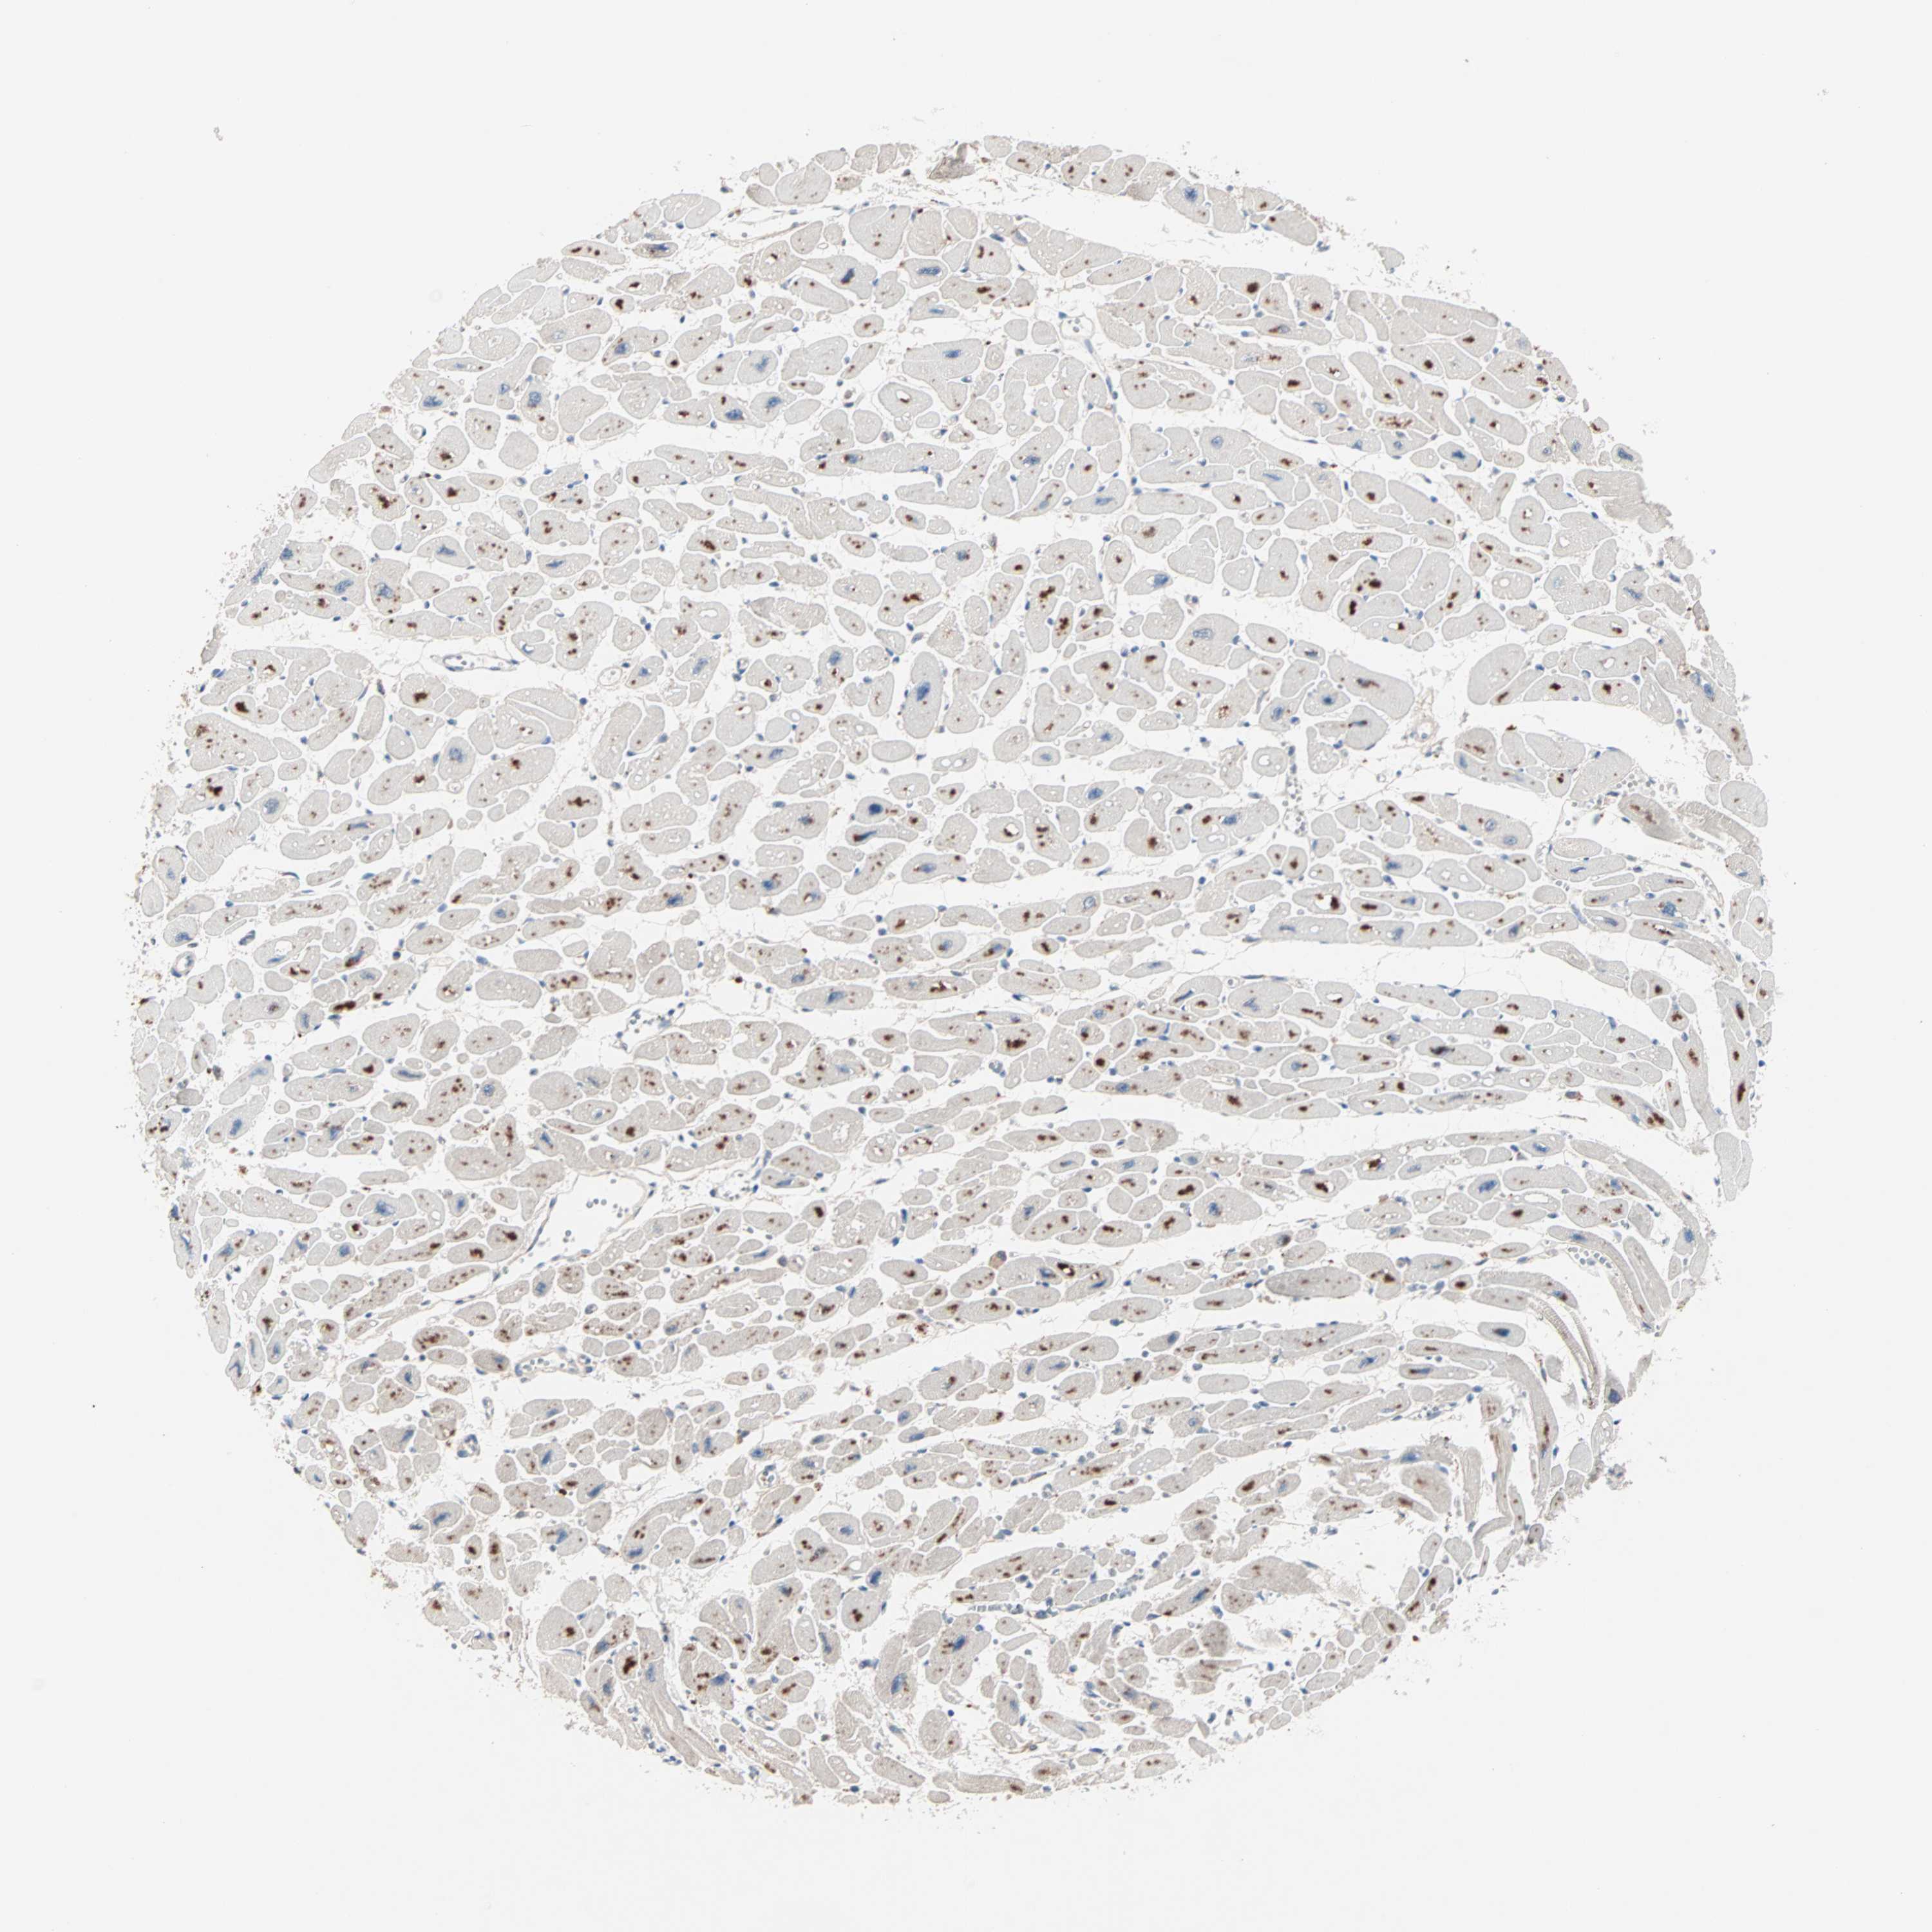

HEART MUSCLE - Antibody stainingi

Antibody staining in the annotated cell types in the current human tissue is reported as not detected, low, medium, or high, based on conventional immunohistochemistry profiling in selected tissues. This score is based on the combination of the staining intensity and fraction of stained cells.

Each image is clickable and will lead to virtual microscopy that enables deeper exploration of all samples and also displays staining intensity scores, fraction scores and subcellular localization as well as patient and tissue information for each sample.

Antibody HPA069341Antibody CAB007781

Cardiomyocytes Not detectedNot detected